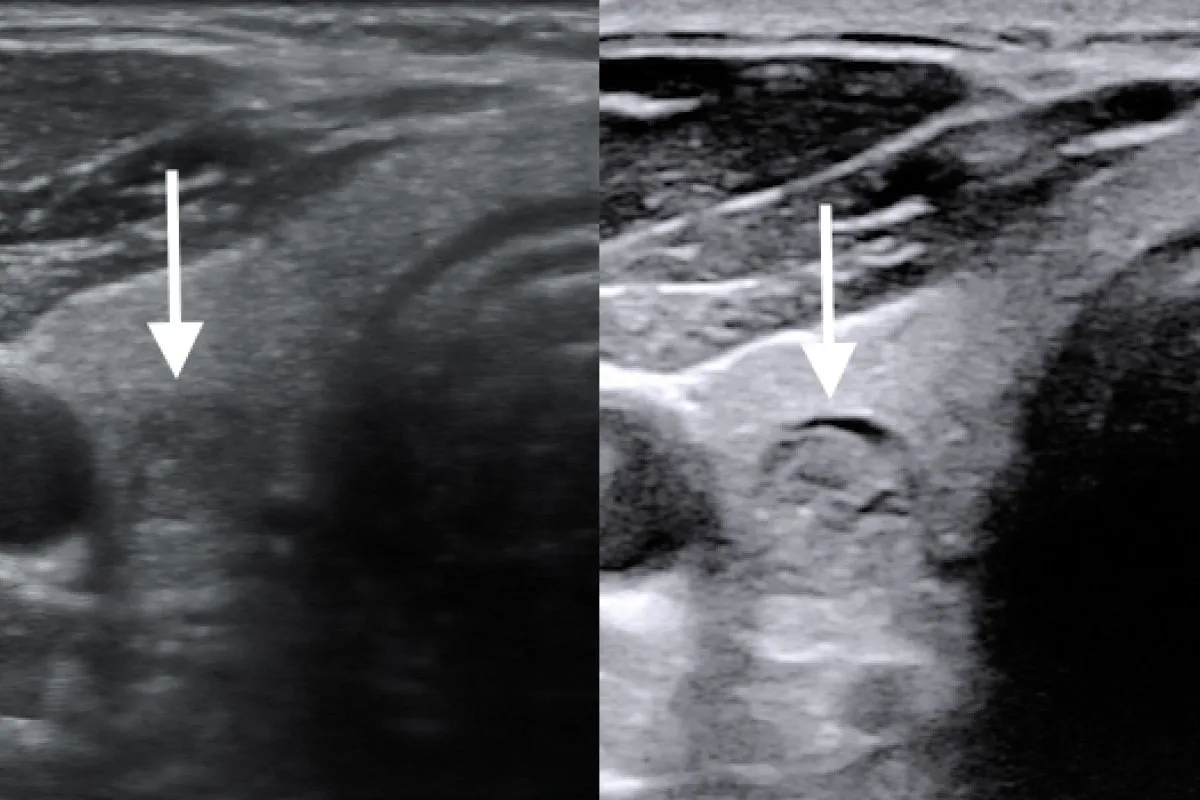

Co pokaże USG tarczycy i kiedy konieczna jest biopsja?

USG tarczycy to nieinwazyjne badanie obrazowe, które pozwala na dokładną ocenę wielkości, kształtu i struktury gruczołu. Dzięki niemu można wykryć obecność guzków, ocenić ich wielkość, echogeniczność i unaczynienie. USG jest również pomocne w monitorowaniu zmian w tarczycy. Jeśli podczas badania USG wykryte zostaną podejrzane guzki, endokrynolog może zlecić biopsję aspiracyjną cienkoigłową (BACC). Polega ona na pobraniu niewielkiej próbki komórek z guzka za pomocą cienkiej igły, pod kontrolą USG. Pobrany materiał jest następnie analizowany pod mikroskopem, co pozwala ocenić, czy zmiana ma charakter łagodny, czy złośliwy.